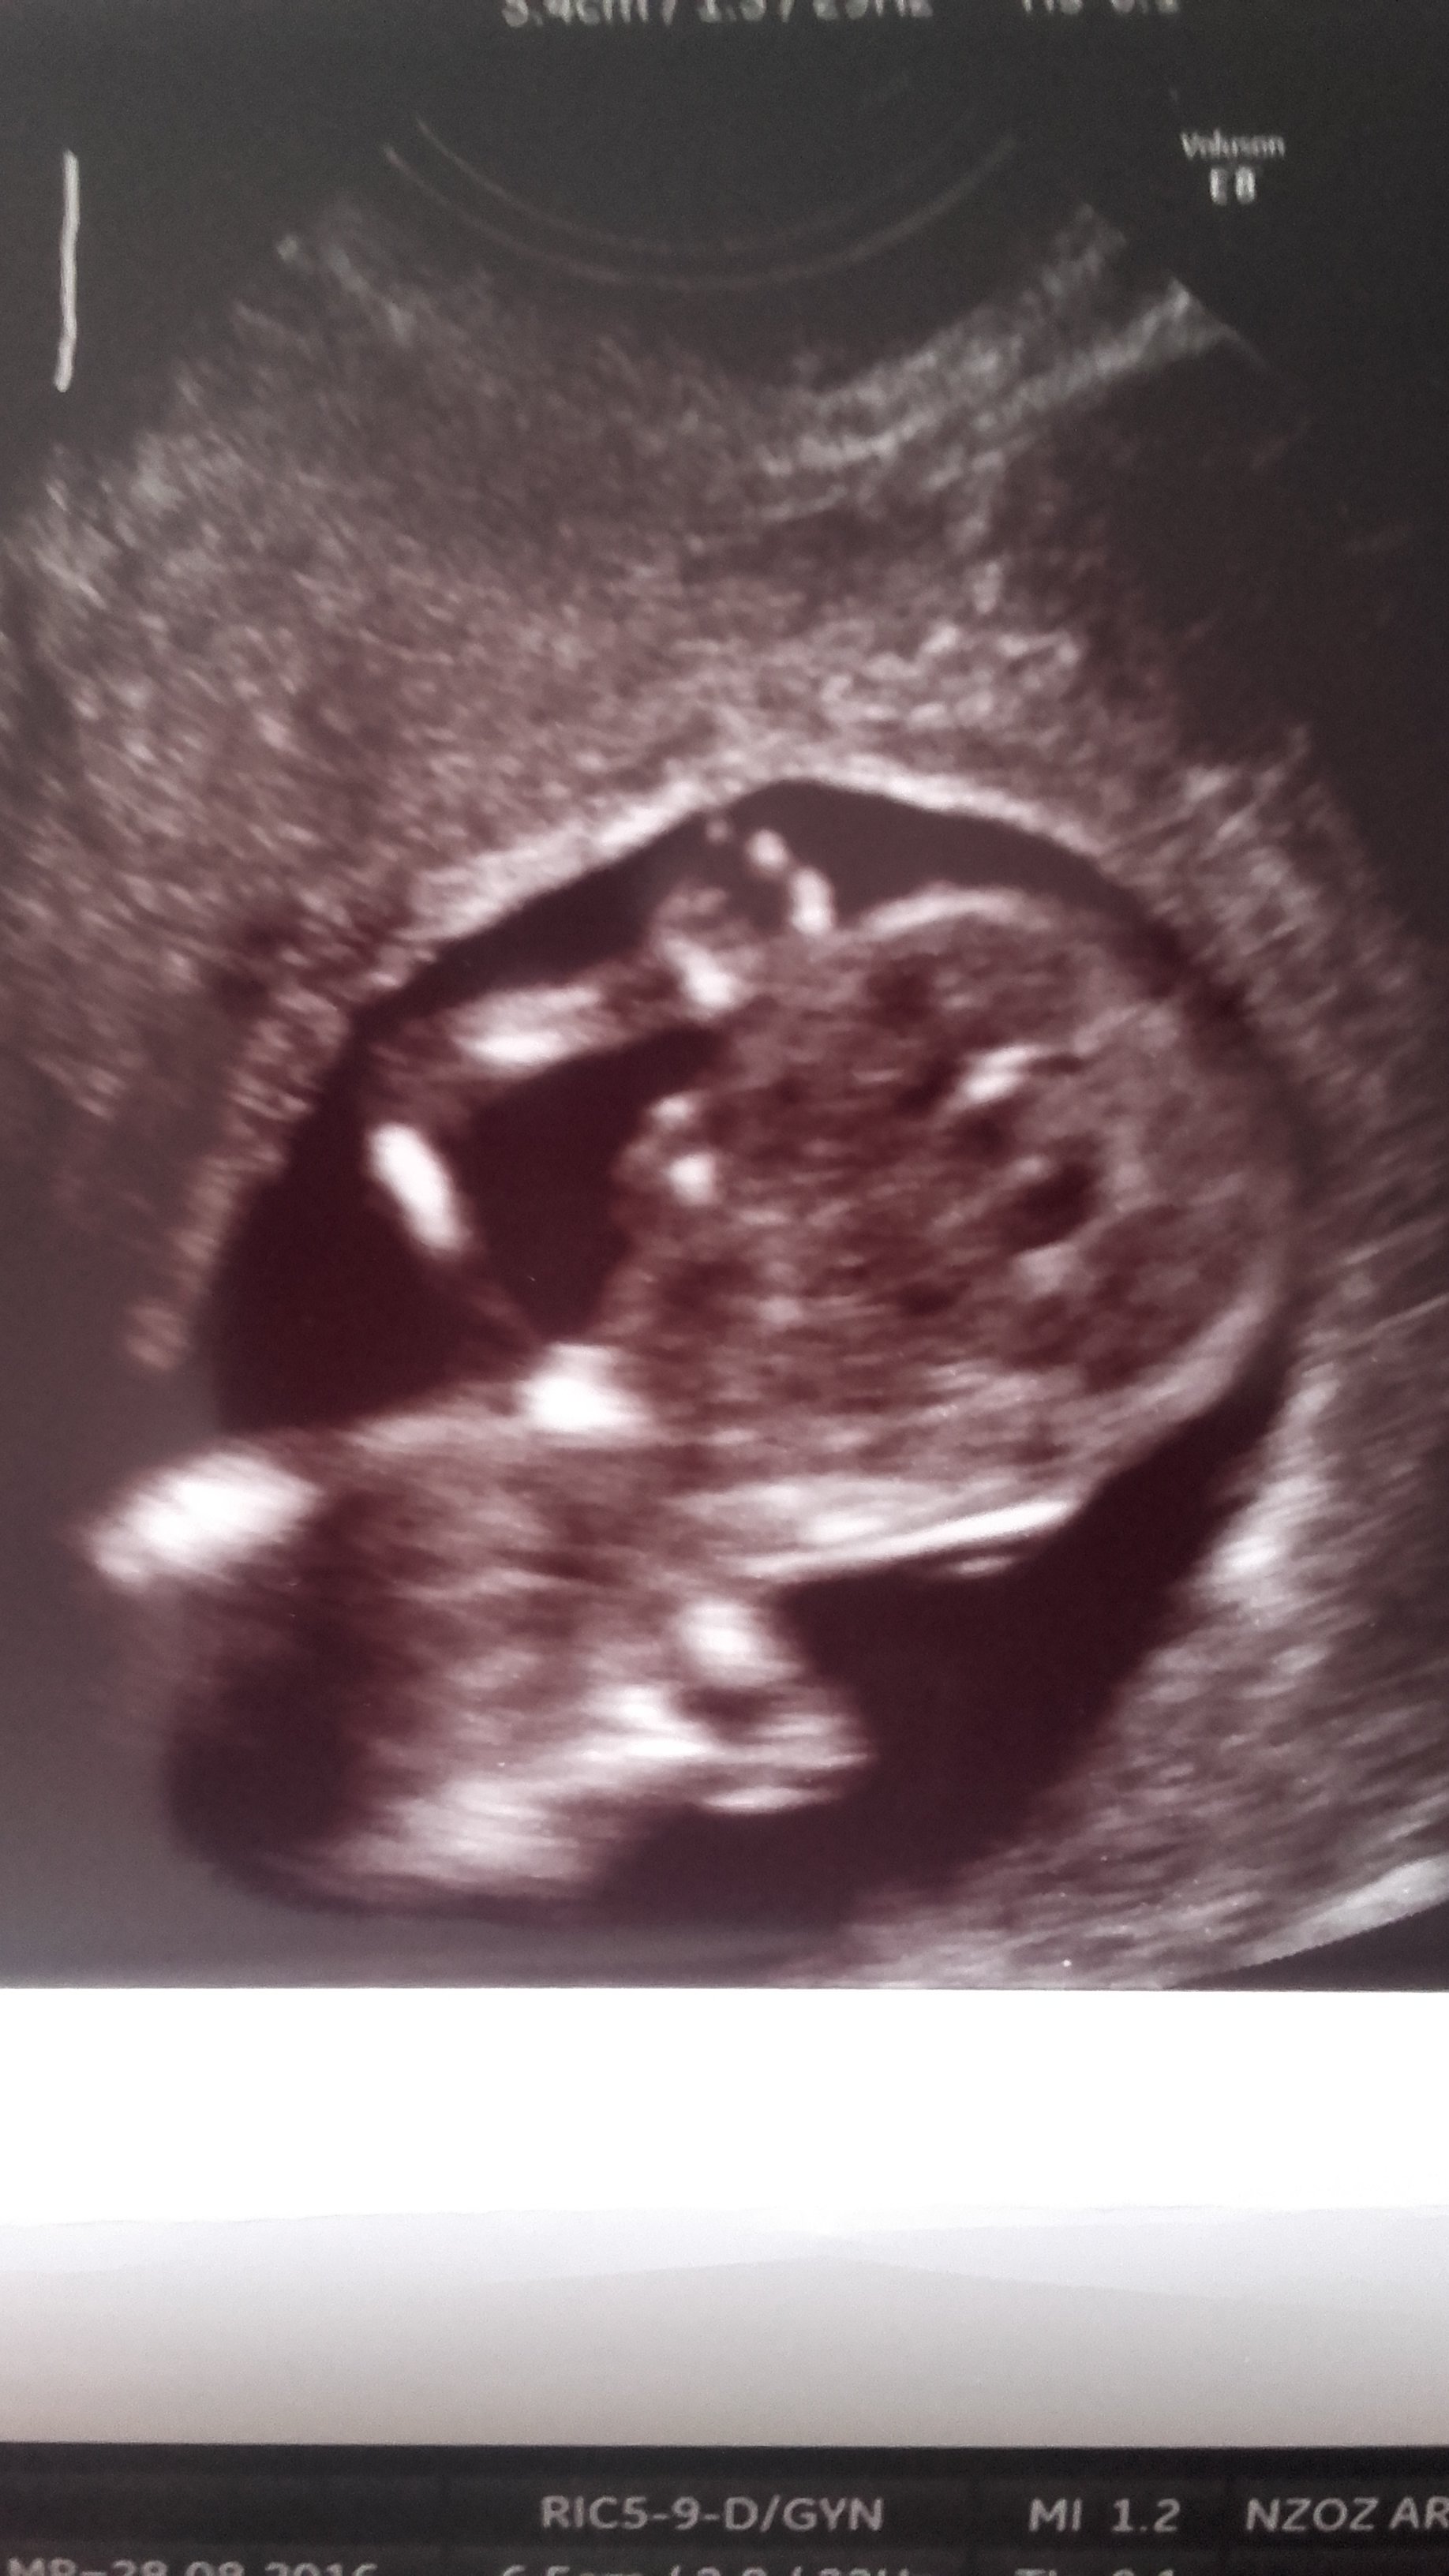

21:Marley - usg pecherzykowo- serduszkowe